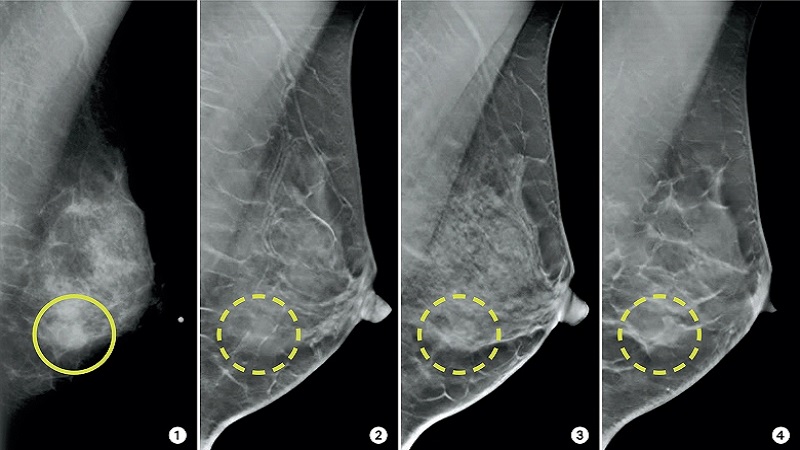

ماموگرافی دوطرفه یک ابزار غربالگری است که برای بررسی ناهنجاری های بافت پستان استفاده می شود. این معاینه امکان تجسم ساختار هر سینه را فراهم می کند که در 2 موقعیت مختلف عکسبرداری با اشعه ایکس انجام می شود تا کل حجم غده پستانی قابل مشاهده باشد تا هرگونه ناهنجاری تشخیص داده شود.

معمولاً دو عکس از هر سینه برای مشاهده سینه از زوایای مختلف گرفته می شود: یکی از جلو و دیگری از پهلو.

تصاویر در موقعیت های مختلف با بستن نازل بین دو صفحه گرفته می شود. ماموگرافی از بالا به پایین (Craniocaudal-CC) و ماموگرافی جانبی (Mediolateral-MLO) اغلب گرفته می شود. هرچه نازل بهتر فشرده شود، تصویر بهتری به دست می آید. با این حال، نباید اجازه داد که بیمار در طول فشرده سازی بیش از حد متحمل شود.